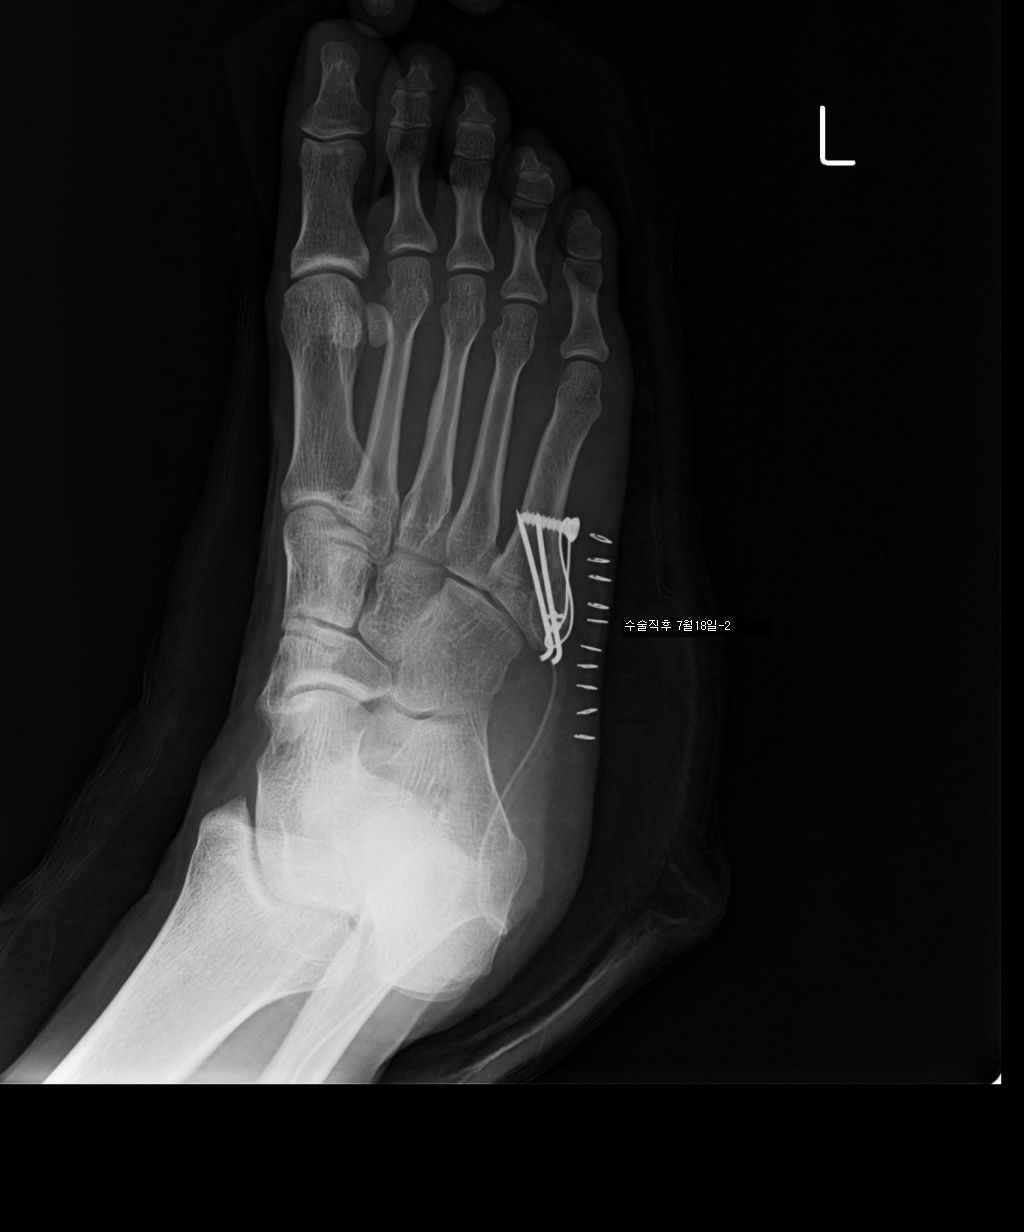

수술한지 100일 정도 됩니다.

7/17 : 출근 중 지하철 계단에서 구르는 사고로 좌측제5중족골기저부 골절

7/18 : 관헐적 정복 및 금속내고정술  시행 및 반깁스 (2주)

아래는 그간의 사진입니다. 제 눈은로는 수술직후의 사진과 3개월후의 사진의 차이를 잘 모르겠네요..